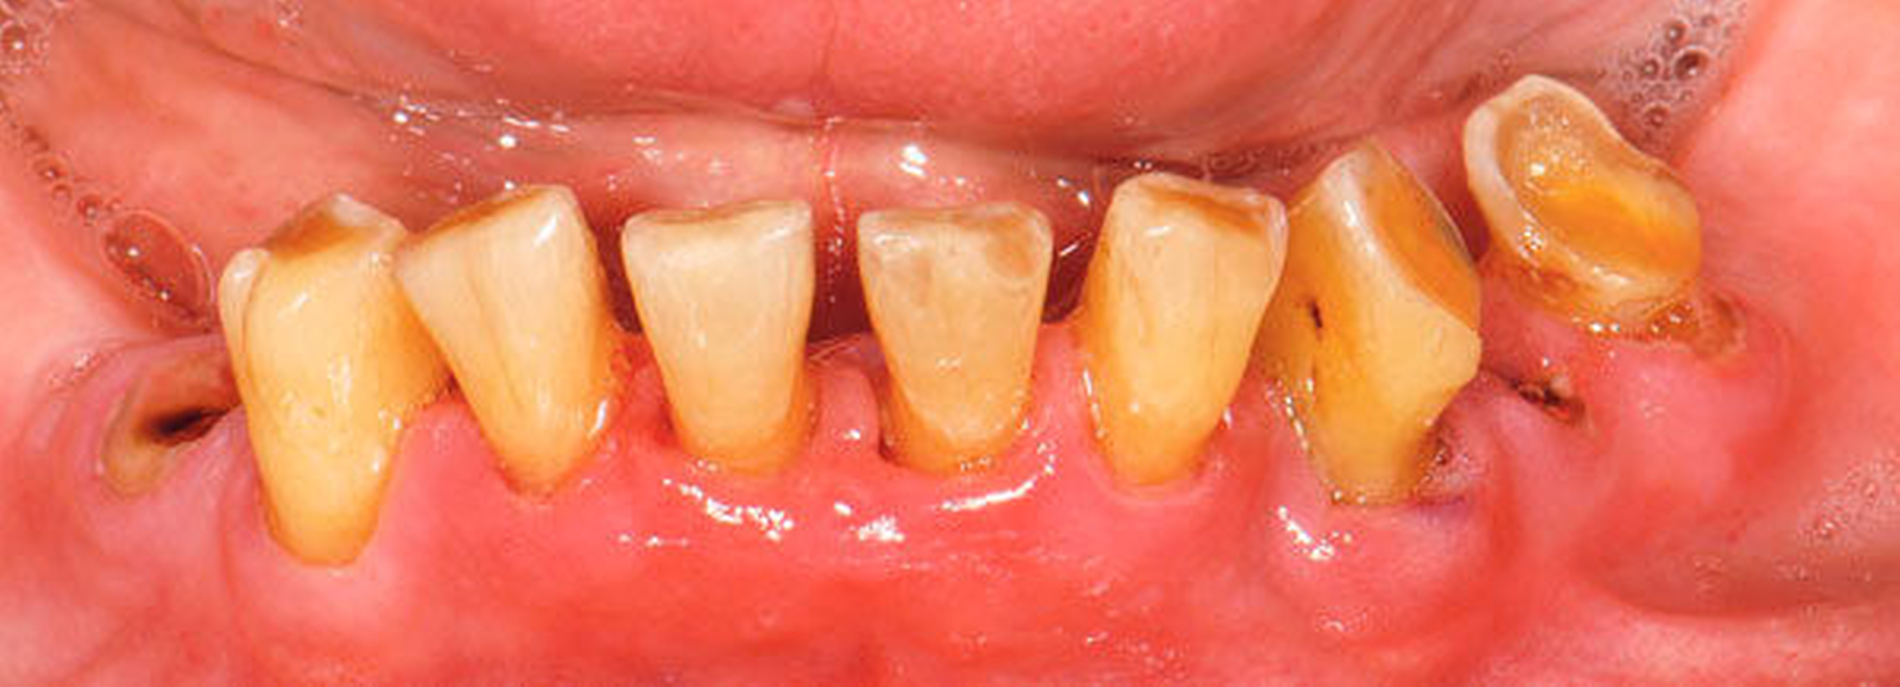

Bei älteren Patienten mit (infolge geistiger Einschränkung) vernachlässigter Mundhygiene, exemplarisch in Abbildung 5 dargestellt, wird zuweilen eine Extraktion sämtlicher Zähne vorgenommen. Eine anschließende prothetische Versorgung ist in solchen Fällen wegen mangelnder Adaptationsfähigkeit oftmals nicht mehr möglich. Dies hat zur Konsequenz, dass die Betroffenen in ihrem Aussehen, ihrer Sprachfunktion und ihrer Fähigkeit zur Nahrungsaufnahme noch eingeschränkter sind als vorher, verbunden mit vielerlei Nachteilen im psycho-sozialen Umfeld.

Wenn irgend möglich, sollte deshalb erwogen werden, einen Erhaltungsversuch wenigstens bei den gut zugänglichen Schneide- und Eckzähnen vorzunehmen, auch wenn die Prognose unsicher ist und Rezidive der Wurzelkaries zu erwarten sind. Die in Abbildung 5 gezeigte Patientin lebte zunächst noch zu Hause und wurde von einer Pflegeperson täglich betreut. Nach Umzug in ein Pflegeheim wird sie von ihrer ehemaligen Pflegerin nach wie vor ein- bis zweimal wöchentlich aufgesucht. Die Pflegerin nimmt bei ihr ein- bis zweimal wöchentlich eine Zahnreinigung mittels Zahnbürste und Interdentalraumbürsten vor, was mit einem Zeitaufwand von jeweils maximal fünf bis zehn Minuten verbunden ist. Obwohl sich nach zwei Jahren an einigen Zähnen ein Kariesrezidiv eingestellt hat, konnte der Zahnbestand gehalten werden.

Abbildung 4: Anliegen eines 76,5-jährigen Patienten (Anfrage per E-Mail). Zitat: „Mich plagt eine … Entzündung des Mundraums, die auch das Zahnfleisch meiner Zahnstummel angreift, weshalb ich nur noch Breiartiges zu essen vermag. Ein Angsthase wie ich geht zum Zahnarzt NUR unter dem Eindruck akuter Schmerzen!“

Damit wird die Hygienefähigkeit zumindest partiell verbessert und Spielraum für künftige Planungen und Vorgehensweisen unter besseren Bedingungen belassen. Das Procedere ist in den Abbildungen 4 und 5 beschrieben. Bei dem in Abbildung 4 vorgestellten Patienten lag eine Oralphobie im Seniorenalter vor. Die Verlaufsbeschreibung macht deutlich, dass selbst im fortgeschrittenen Alter eine Adaptation an zahnärztliche Interventionen im Einzelfall noch möglich ist.